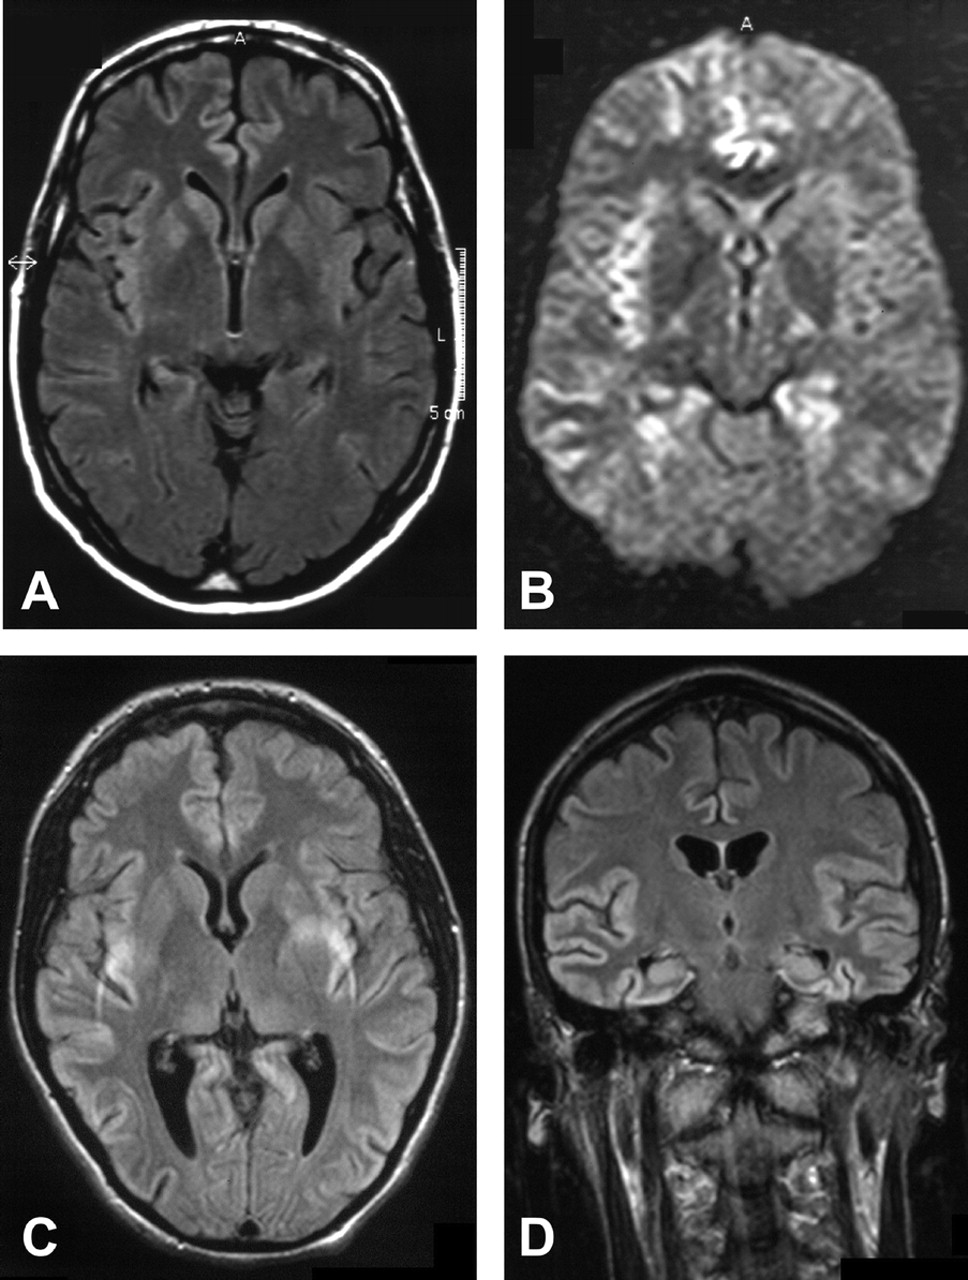

我们评估了天赋和T2图像7的9个病人。一个醉酒驾车和一个质子density-weighted形象(PD)除了可用(表2和图1中,通过D)。除了一个病人(例3)检查后整体疾病持续时间的三分之一。所有七个病人显示皮层信号增加,而只有两个病人显示hyperintense基底神经节。受影响的大脑区域通常是颞叶(所有的病人),脑岛和海马体(6例),其次是额叶、顶叶、枕叶和扣带回(5例)。病人呈现焦迹象,相应的MRI大脑区域受到影响:额叶是显示失用症和失语症患者的影响,在病人显示hypacusis颞叶,枕叶视觉障碍患者。

下面的案例报告是选择来说明一个典型的MRI显示信号增加大脑皮层区域在一个案例中(8例)和SPECT异常在另一个(例4)。

他住院两个月后出现症状。核磁共振成像显示信号增加额叶和颞叶T2。天赋还显示一个信号增加parieto-occipital叶和海马。开始三个月后,病人被送去精神病院,因为他行为异常发达,成为害怕电。四个月后开始,他的神经状态仍然是正常的,除了抑制眉间反射和轻度痴呆(21 30分的细微精神状态检查)。当时MRI显示更少的参与fronto-parieto-occipital叶但轻微的信号变化的基底神经节(右尾状核头在左边)(见图1一个)。SPECT显示低灌注的左颞叶。但是没有PSWCs脑电图显示间歇性theta-delta活动。病人在疾病发作10个月后死亡。